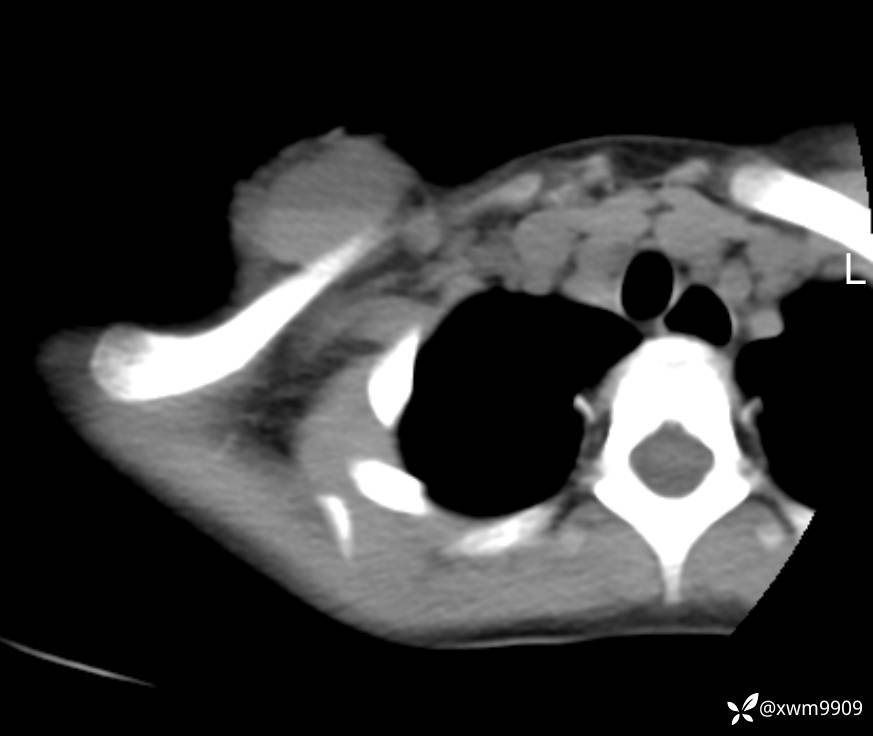

2024-03-20,女,6岁。因“发现右侧胸部肿物伴疼痛1天”入院。

1、患儿为女性儿童,无明确外伤史(此处与门诊病史相反),现发现右侧胸部肿物、疼痛。

2、现病史:家属代诉昨日洗澡时发现右胸肿物,压痛明显,查DR:未见明显异常,自行予云南白药,症状稍好转。临床拟:锁骨周围血肿收入院。

3、查体,右锁下方可及一约5x6Cm肿物,软丶边清丶未见明显发红,肤温不高,压痛明显,不可推动,稍有波动感。其他无特殊。

CT:

2、CT、MR肿块内可见液-液平面,常见有哪些疾病。